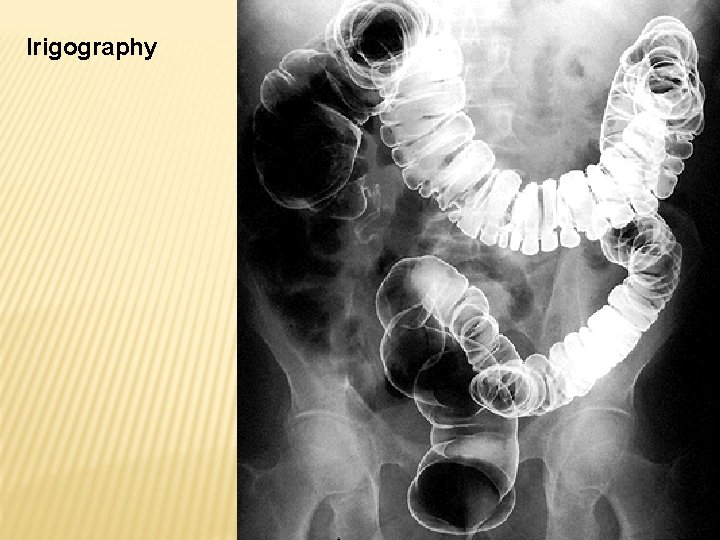

INTESTINUM CRASSUM -caecum -appendix vermiformis -colon ascendens -flexura coli dextra (hepatica) -colon transversum -flexura coli sinistra (lienalis) -colon descendens -colon sigmoideum -rectum

Plicae semilunares Haustra coli Taenia mesocolica Taenia omentalis Taenia libera Appendices omentales/epiploicae

Irigography